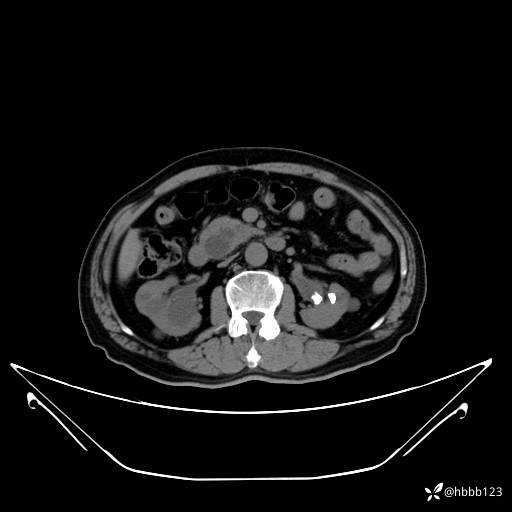

门诊完善上腹部CT平扫+增强扫描:

门脉期: